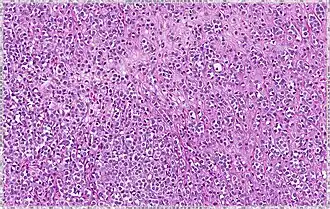

| Solid | 10% | Sheets of classical-appearing cells with little intervening stroma | |

| Pleomorphic | Classical-appearing but with pleomorphic cells. It may include signet-ring cells, or plasmacytoid cells (pictured) which have abundant cytoplasm and eccentric nuclei. |  |